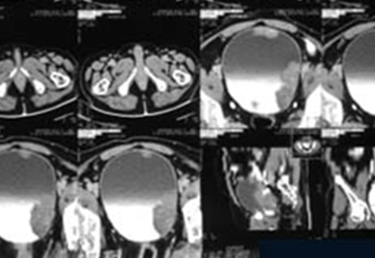

CT Urography – will detect the presence, depth and type of bladder cancer with functioning of urinary system.

If Transitional Cell Carcinoma – of the Bladder is detected on Biopsy, subsequent evaluation will be done for staging, grading and distant spread of bladder cancer